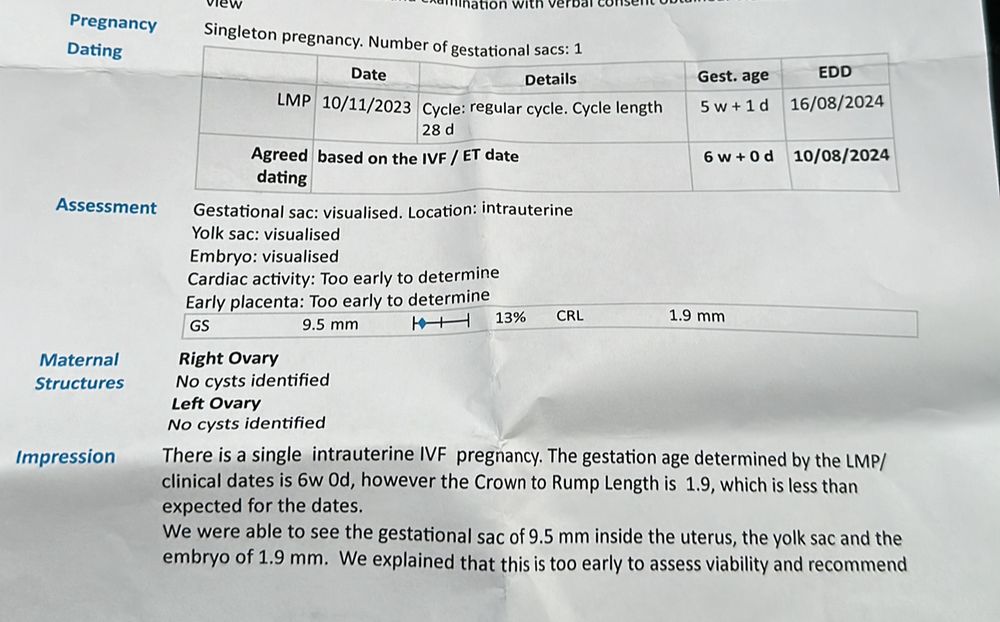

Здравствуйте девочки - вопрос возможно глупый но ситуация странная. Итак, в прошлую субботу мне исполнилось 3 недели после 5-дневного переноса эмбрионов. Итак, сканирование показало эмбрион размером 1,9 мм и плодное яйцо диаметром 9,5 мм. Я сдавала ХГЧ 4 раза за этот период и все в порядке. Вчера сделала сканирование (то есть через 4 недели после переноса) и уже виден только мешок 15,3 мм, а эмбрион исчез? Может ли быть такое - одну неделю эмбрион существует, а вторую неделю чудесным образом исчезает? У меня не было ни кровотечения, ни болей в животе. Прикрепляю фото первого скана с эмбрионом и второго вчерашнего скана без эмбриона. Врач рекомендовал мне продолжить лечение до следующего четверга и сделать еще одно сканирование через 5 недель после переноса. Любые предложения и советы будут оценены по достоинству. Большое спасибо

это и скан и анализ крови в один день

это и скан и анализ крови в один день

Ангелина, и сейчас прикреплю и рапорт где есть эмбрион

Ангелина, и сейчас прикреплю и рапорт где есть эмбрион